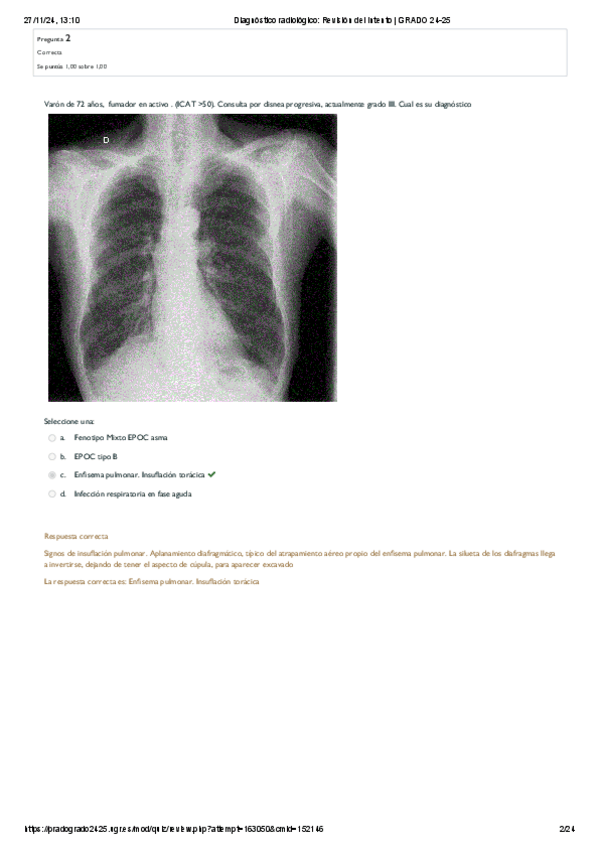

Tipo D